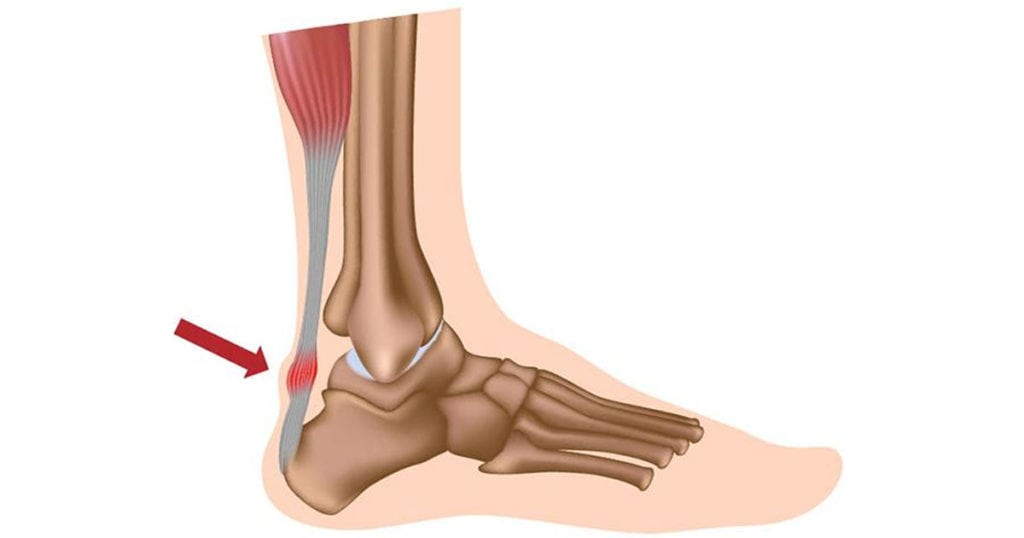

Ахиллово сухожилие — связующее звено между пяточной костью и мышцами икры. За счет этого мощного соединительнотканного тяжа обеспечивается подвижность голеностопа. Он помогает суставу выдерживать интенсивные статические и динамические нагрузки. Но при превышении предела прочности целостность волокон нарушается, а ахиллово сухожилие утрачивает способность стабилизировать стопу. Ведущий симптом растяжения — острая, пронизывающая боль, а затем на травмированном участке формируется отек и обширная гематома.

Ахиллово сухожилие — структура прочная, но не эластичная, поэтому растягиваться не может. Волокна соединительного тяжа рвутся, а в особо тяжелых случаях полностью отрываются от костного основания. Такие травмы диагностируются чаще у пациентов 30-50 лет, которые активно занимаются спортом.

Ахиллово сухожилие является самым крупным в опорно-двигательной системе человека, а формируют его камбаловидная и икроножная мышцы. Основная функция тяжа — подъем пятки во время движения. Он также участвует в опускании передней части стопы. Если бы этого тяжа не было, то человек не смог бы:

Главная причина разрыва этого прочного тяжа — резкое сокращение икроножной и камбаловидной мышц. Такая ситуация возникает во время прыжка или бега при старте, при падении из-за сильного сгибания стопы с тыльной стороны. Волокна разрываются в результате прямой травмы, например, удара ногой или тяжелым предметом.